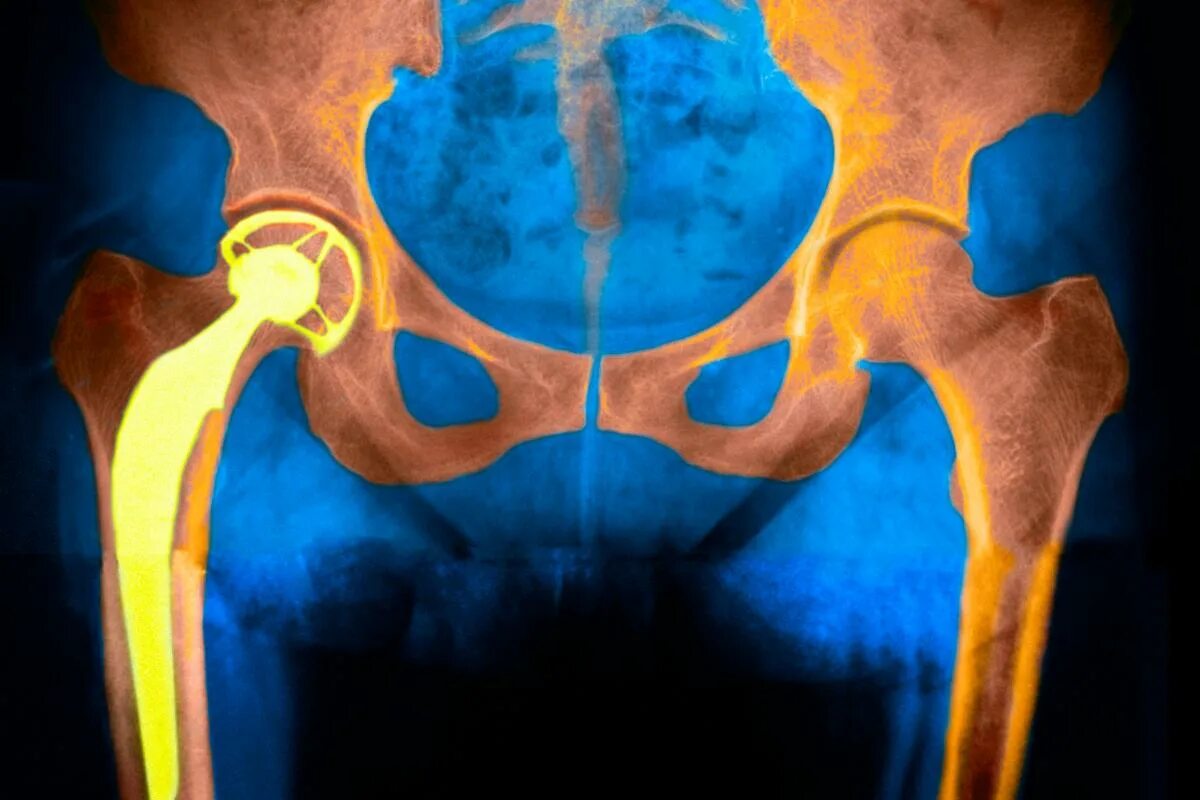

Эндопротезирование тазобедренного сустава видео